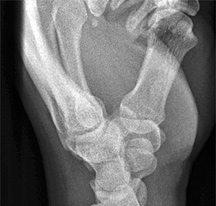

Figure 3: PA wrist

When evaluating the PA view of the wrist (Figure 3), the joint spaces of the wrist have a width of 2 mm or less. Only the radiocarpal joint is slightly wider. The carpometacarpal joints are slightly narrower than the midcarpal joints. The capitolunate joint is considered the baseline joint width to which other joint spaces can be compared. Make sure to look at all of them: the radiocarpal, the proximal intercarpal, the midcarpal, the distal intercarpal and the carpometacarpal joint spaces.